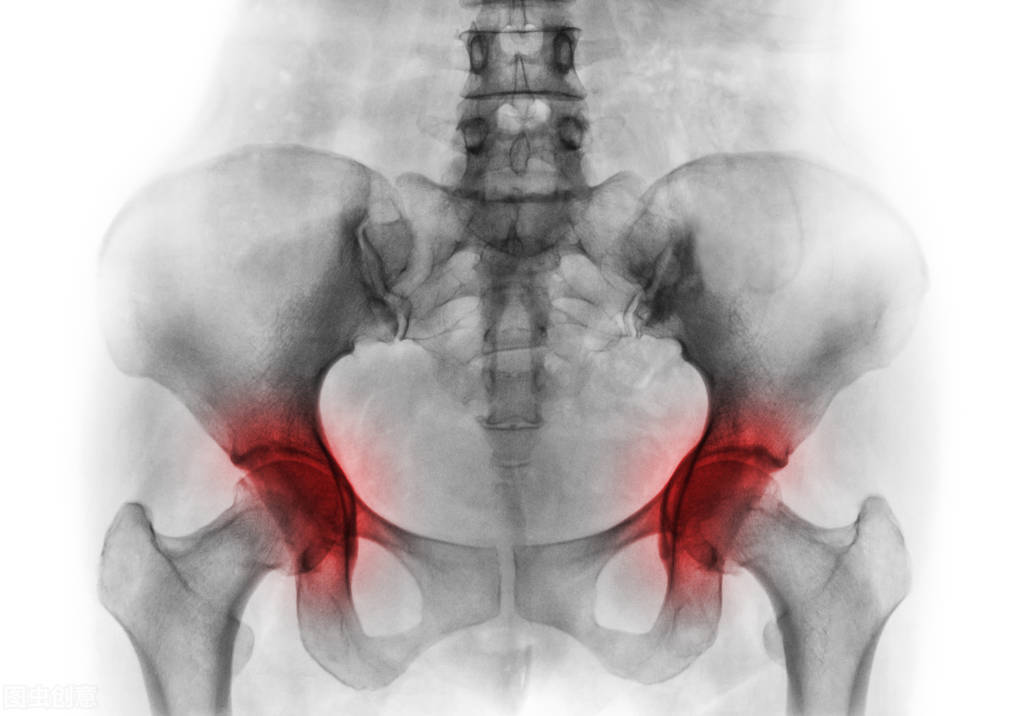

就比如在2003年的非典时期,医生治疗无策的时候,只能大剂量地用激素治疗,虽然疾病得到了控制,但是很多人并发了股骨头坏死等很多的并发症。那我们接下来就来具体看看是不是激素搞的鬼?一起来学习一下糖皮质激素是何方神圣!

红色部位为股骨头

(5)骨质疏松、股骨头坏死、肌肉萎缩、伤口愈合迟缓等;